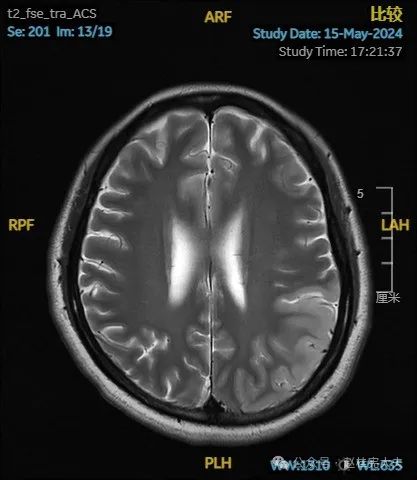

入院后给予精氨酸,左卡尼丁,辅酶Q10,维生素E等治疗。患者病情稳定好转中,2天后意识清楚,语言表达仍欠佳。当天复查颅脑磁共振如下:

以上为患者发病后3次的颅脑磁共振片子,临床诊断基本上可以确认了,希望患者逐渐恢复!